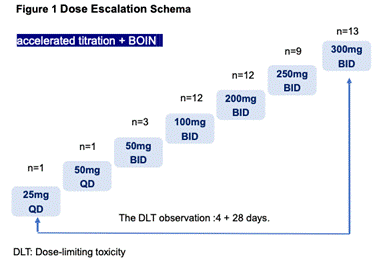

иҜҘв… /в…Ўжңҹз ”з©¶е…ұзәіе…Ҙ51дҫӢRETзӘҒеҸҳе®һдҪ“зҳӨжӮЈиҖ…�пјҢпјҢпјҢпјҢ�пјҢ�пјҢеҮӯиҜҒеҠ йҖҹж»ҙе®ҡе’ҢBOINи®ҫи®Ў�пјҢпјҢпјҢпјҢ�пјҢ�пјҢеҲҮеҗҲжқЎд»¶зҡ„жӮЈиҖ…жҺҘеҸ—BYS10жІ»з–—�пјҢпјҢпјҢпјҢ�пјҢ�пјҢйҖҗж—ҘеүӮйҮҸдёә25иҮі600 mg�гҖӮгҖӮгҖӮгҖӮ�гҖӮз ”з©¶зҡ„дё»иҰҒз»ҲзӮ№еҢ…жӢ¬жё…йқҷжҖ§гҖҒиҖҗеҸ—жҖ§гҖҒжңҖеӨ§иҖҗеҸ—еүӮйҮҸпјҲMTDпјүе’ҢеүӮйҮҸйҷҗеҲ¶жҖ§жҜ’жҖ§пјҲDLTпјү�гҖӮгҖӮгҖӮгҖӮ�гҖӮж¬ЎиҰҒз»ҲзӮ№еҢ…жӢ¬иҚҜд»ЈеҠЁеҠӣеӯҰпјҲPKпјүе’Ңиө·жәҗжҠ—иӮҝзҳӨжҙ»жҖ§[1]�гҖӮгҖӮгҖӮгҖӮ�гҖӮ

е…Ҙз»„жӮЈиҖ…ж—ўеҫҖжҺҘеҸ—иҝҮжүӢжңҜгҖҒж”ҫз–—жҲ–еҢ–з–—жІ»з–—�пјҢпјҢпјҢпјҢ�пјҢ�пјҢе…¶дёӯ�пјҢпјҢпјҢпјҢ�пјҢ�пјҢ78.4%пјҲn=40пјүзҡ„жӮЈиҖ…дёәNSCLCжӮЈиҖ…�пјҢпјҢпјҢпјҢ�пјҢ�пјҢз”·жҖ§дёҺеҘіжҖ§жӮЈиҖ…жҜ”дҫӢзӣёиҝ‘�пјҢпјҢпјҢпјҢ�пјҢ�пјҢ21.6%пјҲN=11пјүзҡ„жӮЈиҖ…жіӣиө·CNSиҪ¬з§»[1]�гҖӮгҖӮгҖӮгҖӮ�гҖӮ

иЎЁ1.жӮЈиҖ…еҹәзәҝзү№еҫҒ